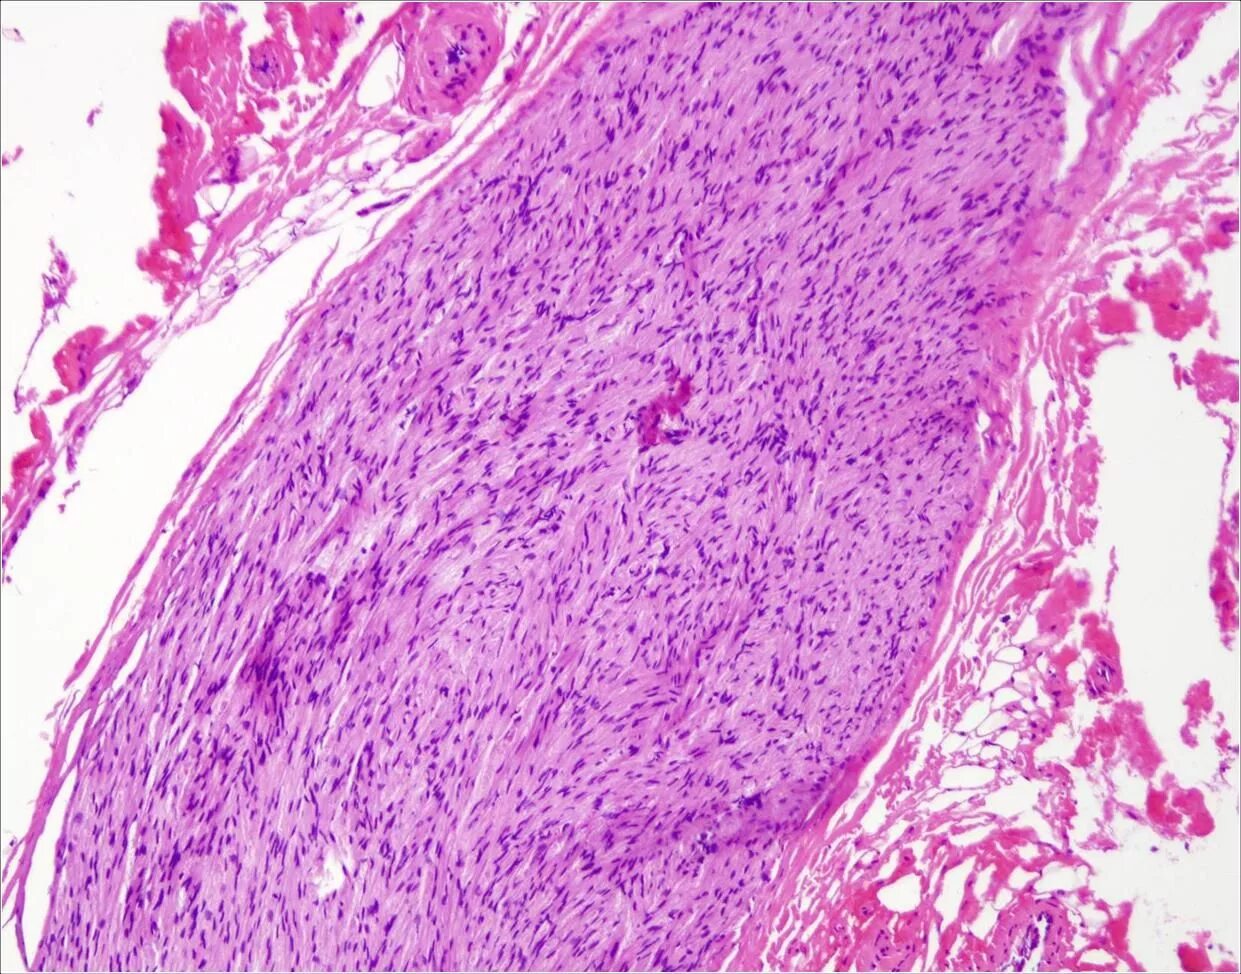

Синовиомы